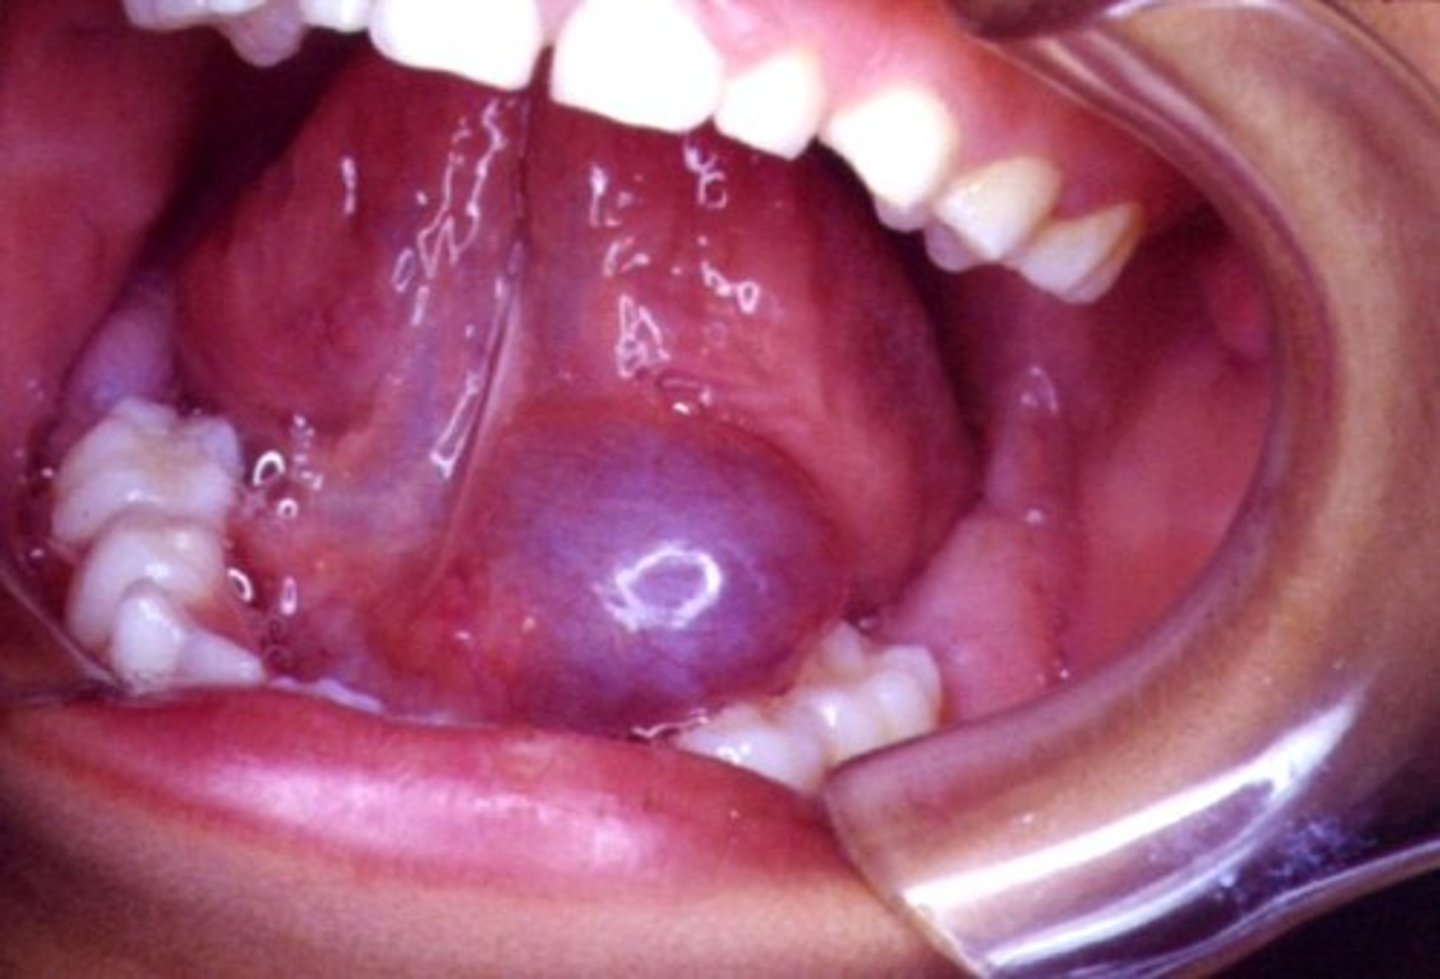

what is a ranula

a mucocele that occurs in the floor of the mouth

- arise from the sublingual gland

what are the clinical manifestations of a ranula (physical examination)

- swollen lesion in the floor of the mouth

- blue (deeper lesions are normal color)

- dome-shaped

what is the treatment for a cervical (plunging) ranula

surgical removal of feeding gland